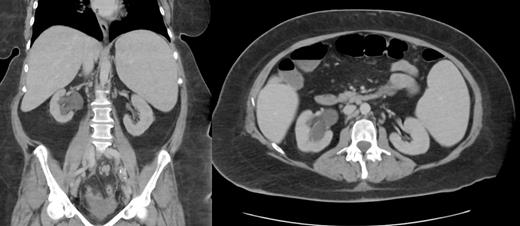

Case Description: We present a rare and intriguing case of a 51-year-old female admitted for acute on chronic microcytic anemia, with accompanying symptoms of decreased oral intake due to nausea, and vomiting, significant weight loss, night sweats, and lower quadrant abdominal pain. Additionally, she reported decreased urinary frequency, urgency. CT imaging of the abdomen and pelvis revealed a large soft tissue mass measuring 7.6 x 4.6 x 5.7 cm in the posterior right pelvic region, resulting in severe hydroureteronephrosis, along with bilateral iliac chain adenopathy, retroperitoneal lymph node enlargement, and severe splenomegaly. CT chest revealed several small lung nodules indicating distant metastasis. Additionally, the patient exhibited elevated levels of LDH, CA 199, and CRP, and decreased hemoglobin levels, indicating the presence of systemic disease. A CT-guided biopsy of the right pelvic mass confirmed the diagnosis of non-Hodgkin malignant lymphoma, specifically of the diffuse large B-cell type. Immunohistochemistry and flow cytometry demonstrated CD20 positivity in the proliferating large cells, consistent with DLBCL, and revealed a kappa-restricted B-cell population expressing CD19, CD20, and kappa surface immunoglobulin light chains. The PET scan showed prominent splenomegaly, adenopathy, and retroperitoneal involvement, corroborating the lymphoma diagnosis. The patient was discharged for outpatient follow-up with oncology with a treatment plan of R-CHOP (rituximab, cyclophosphamide, doxorubicin, vincristine, and prednisone) administered every 3 weeks, omitting rituximab during the first cycle.